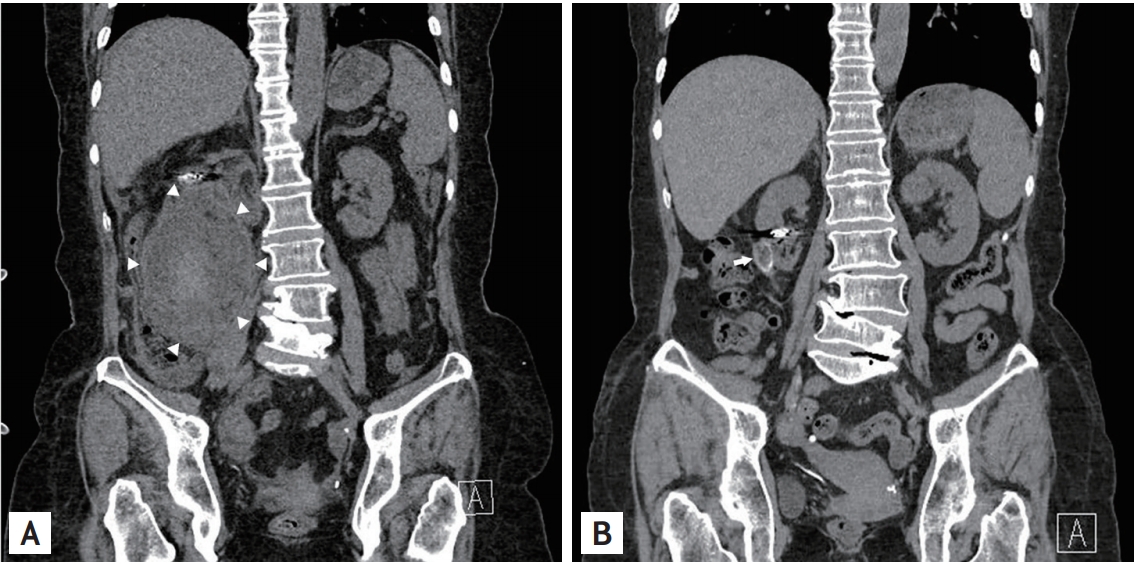

A 61-year-old woman presented at the emergency department with sudden onset abdominal pain. She had a history of hypertension and angiomyolipoma (AML) for 18 years. On physical examination, tenderness in the right upper quadrant was observed. Her blood pressure was 89/54 mmHg and hemoglobin level declined to 7.7 mg/dL from 10.0 mg/dL. We performed abdominopelvic computed tomography (CT) to evaluate the cause of epigastric pain and anemia. In the coronal view on CT, rupture of a giant AML containing hematoma in the lower pole of the right kidney was observed (Fig. 1A). Emergency angiography was performed, and the branch of the right renal artery feeding AML was embolized. After that, the patient’s vital signs and hemoglobin level were stabilized, and she recovered uneventfully. Approximately 3 years after discharge, we performed a follow-up abdominopelvic CT, which revealed near complete disappearance of the prior ruptured AML (Fig. 1B).

Wunderlich syndrome is characterized by spontaneous, non-traumatic retroperitoneal bleeding, and the most frequent cause for this syndrome is AML. AML is known as the most common benign tumor of the kidney, and AMLs of large sizes of > 4 cm are known to be associated with a high risk of bleeding. In the case of life-threatening bleeding from AML, selective angioembolization can provide safe and minimally invasive treatment. Surgical resection, especially if malignancy is suspected, can remove the tumor and prevent repeated bleeding. In the present case, we followed up our patient for whom angioembolization for the ruptured AML was performed and were able to obtain serial CT images. This case shows a serial image of regression of AML several years after angioembolization of the rupture AML.